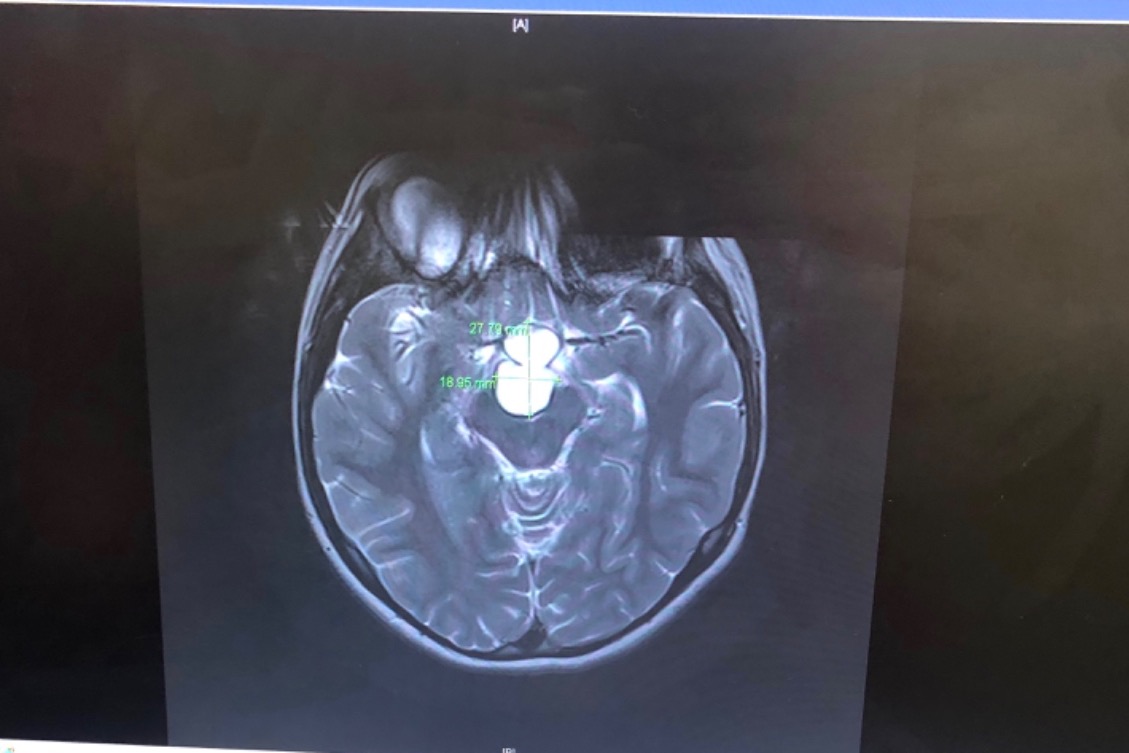

Unfortunately  Kelsey needs to have a

very serious surgery! Apparently she’s

been growing a good size tumor (Craniopharyngioma)on her pituitary gland for

about 4 yrs!